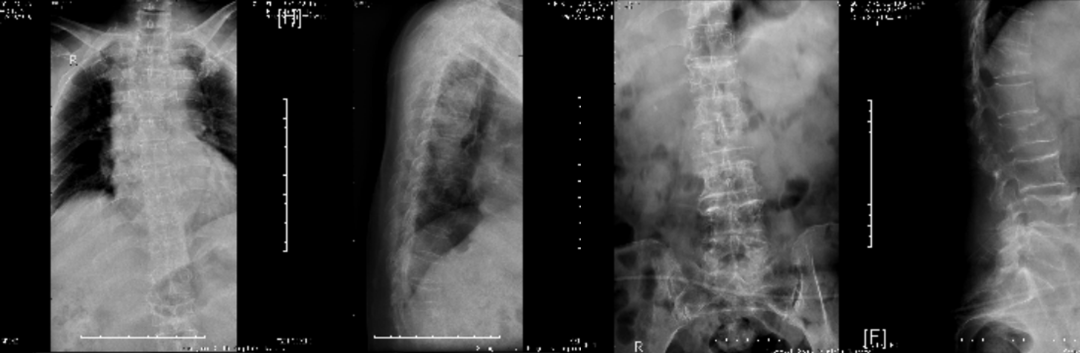

2、利用X线平片发现椎体压缩性骨折(每个医院包括社区均有):

脆性骨折是指受到轻微创伤或日常活动中即发生的骨折,老年男性椎体骨折的患病率与女性相当,椎体骨折的防治在男女两性同等重要。

常规进行X线胸腰椎正侧位摄片漏诊率高,患病率高(上海社区60岁以上17%,建议对50岁以上腰背部疼痛者常规摄片,及早发现椎体骨折。

二、骨质疏松症如何进行影像学检查

X线平片是检出脆性骨折,特别是胸、腰椎压缩性骨折的首选方法。常规胸、腰椎X线侧位摄片的范围应分别包括胸4至腰1和胸12至腰5椎体,基于胸、腰椎侧位X线影像并采用Genant目视半定量判定方法,椎体压缩性骨折的程度分类如下:

X线检查:胸腰椎多发压缩性骨折伴骨质疏松。

X线检查:L2压缩性骨折椎体骨质疏松,头颅未见异常。